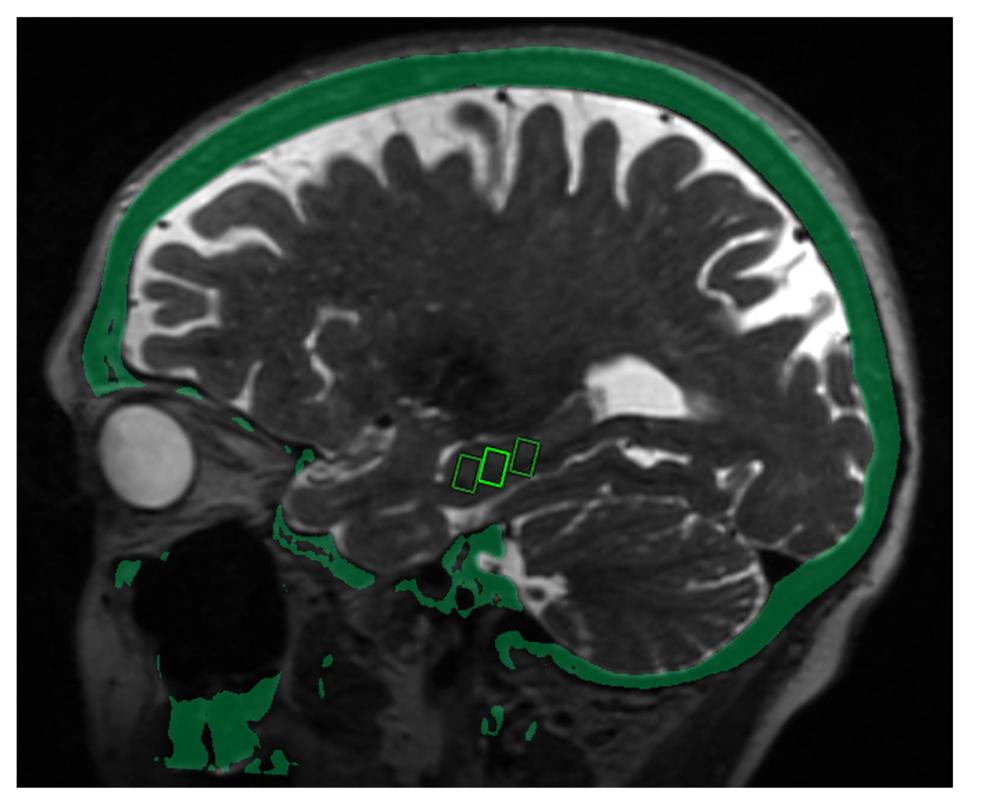

Figure 1. MRI and fused CT image shows three target sites selected in the brain within the hippocampus, a structure critical for memory and affected in patients with Alzheimer's disease.

• Researchers targeted specific sites in the brain critical to memory in three patients with early-stage Alzheimer's disease.

Post-treatment brain MRI confirmed that the blood-brain barrier opened within the target areas immediately after treatment. Closure of the barrier was observed at each target within 24 hours.